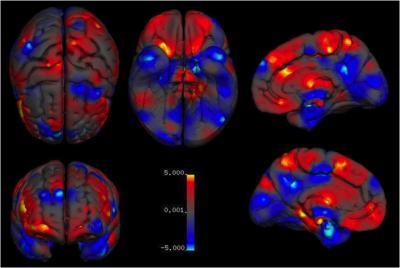

They found that males on average have larger total brain volumes than women (by 8-13%). On average, males had larger absolute volumes than females in the intracranial space (12%; >14,000 brains), total brain (11%; 2,523 brains), cerebrum (10%; 1,851 brains), grey matter (9%; 7,934 brains), white matter (13%; 7,515 brains), regions filled with cerebrospinal fluid (11.5%; 4,484 brains), and cerebellum (9%; 1,842 brains). Looking more closely, differences in volume between the sexes were located in several regions. These included parts of the limbic system, and the language system.

Specifically, males on average had larger volumes and higher tissue densities in the left amygdala, hippocampus, insular cortex, putamen; higher densities in the right VI lobe of the cerebellum and in the left claustrum; and larger volumes in the bilateral anterior parahippocampal gyri, posterior cingulate gyri, precuneus, temporal poles, and cerebellum, areas in the left posterior and anterior cingulate gyri, and in the right amygdala, hippocampus, and putamen.

By contrast, females on average had higher density in the left frontal pole, and larger volumes in the right frontal pole, inferior and middle frontal gyri, pars triangularis, planum temporale/parietal operculum, anterior cingulate gyrus, insular cortex, and Heschl's gyrus; bilateral thalami and precuneus; the left parahippocampal gyrus, and lateral occipital cortex.

An overview of average regional sex differences in grey matter volume. Areas of larger volumes in women are in red and areas of larger volume in men are in blue.

(Photo Credit: Neuroscience and Biobehavioral Reviews)